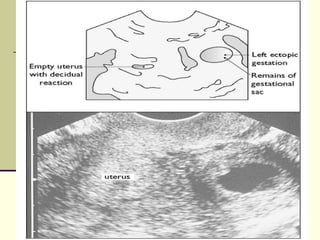

 Ultrasound

 TVS (Transvaginal U/S Scan)

• Can detect 75-80% on initial scan and further 25% on follow

up.

• Transabdominal U/S has a limited role.